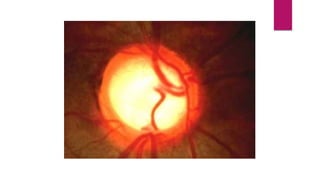

papilledema

Swelling of the optic disc and anterior bulging of the

physiologic cup. Color is pink and hyperemic with disc

margins blurred. Disc vessels are more visible, numerous,

and curve over disc borders. It is a sign not a Dx = can be

seen in more then 1 eye diseases.

DISC

Observe an elevated, edematous disc, with blurred disc

margins, and engorged vessels.

RETINA

A flame retinal hemorrhage close to the disc.

VESSELS

Engorged tortuous veins.